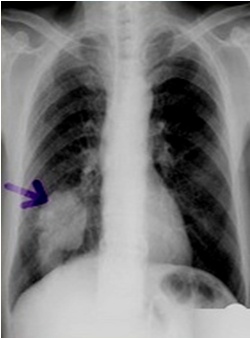

圖中可見右下肺分葉狀腫塊,根據(jù)公式診斷周圍型肺癌